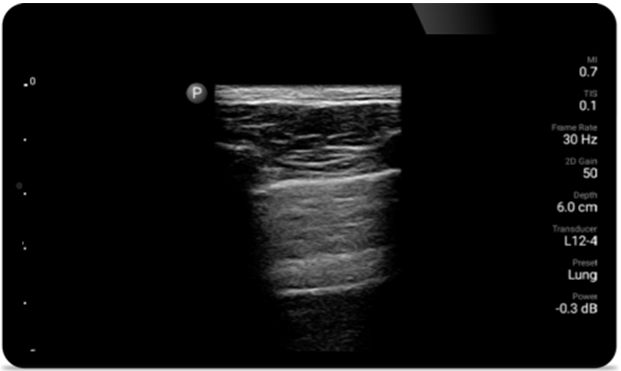

Respire con mayor facilidad con Lumify

Lumify puede ayudar a evaluar a los pacientes más rápido y a mejorar la precisión en el diagnóstico de las causas comunes de disnea y otras afecciones pulmonares.

• Rango extendido de frecuencias de operación de 4 a 1 MHz • 2D, Doppler a color, Modalidad M, XRES avanzado e imágenes armónicas multivariables • Imágenes de alta resolución para aplicaciones abdominales y cardíacas: las optimizaciones de preajustes de imágenes cardíacas, gineco-obstétricas, pulmonares, abdominales y FAST de Lumify ayudan a la tecnología que salva vidas en entornos prehospitalarios